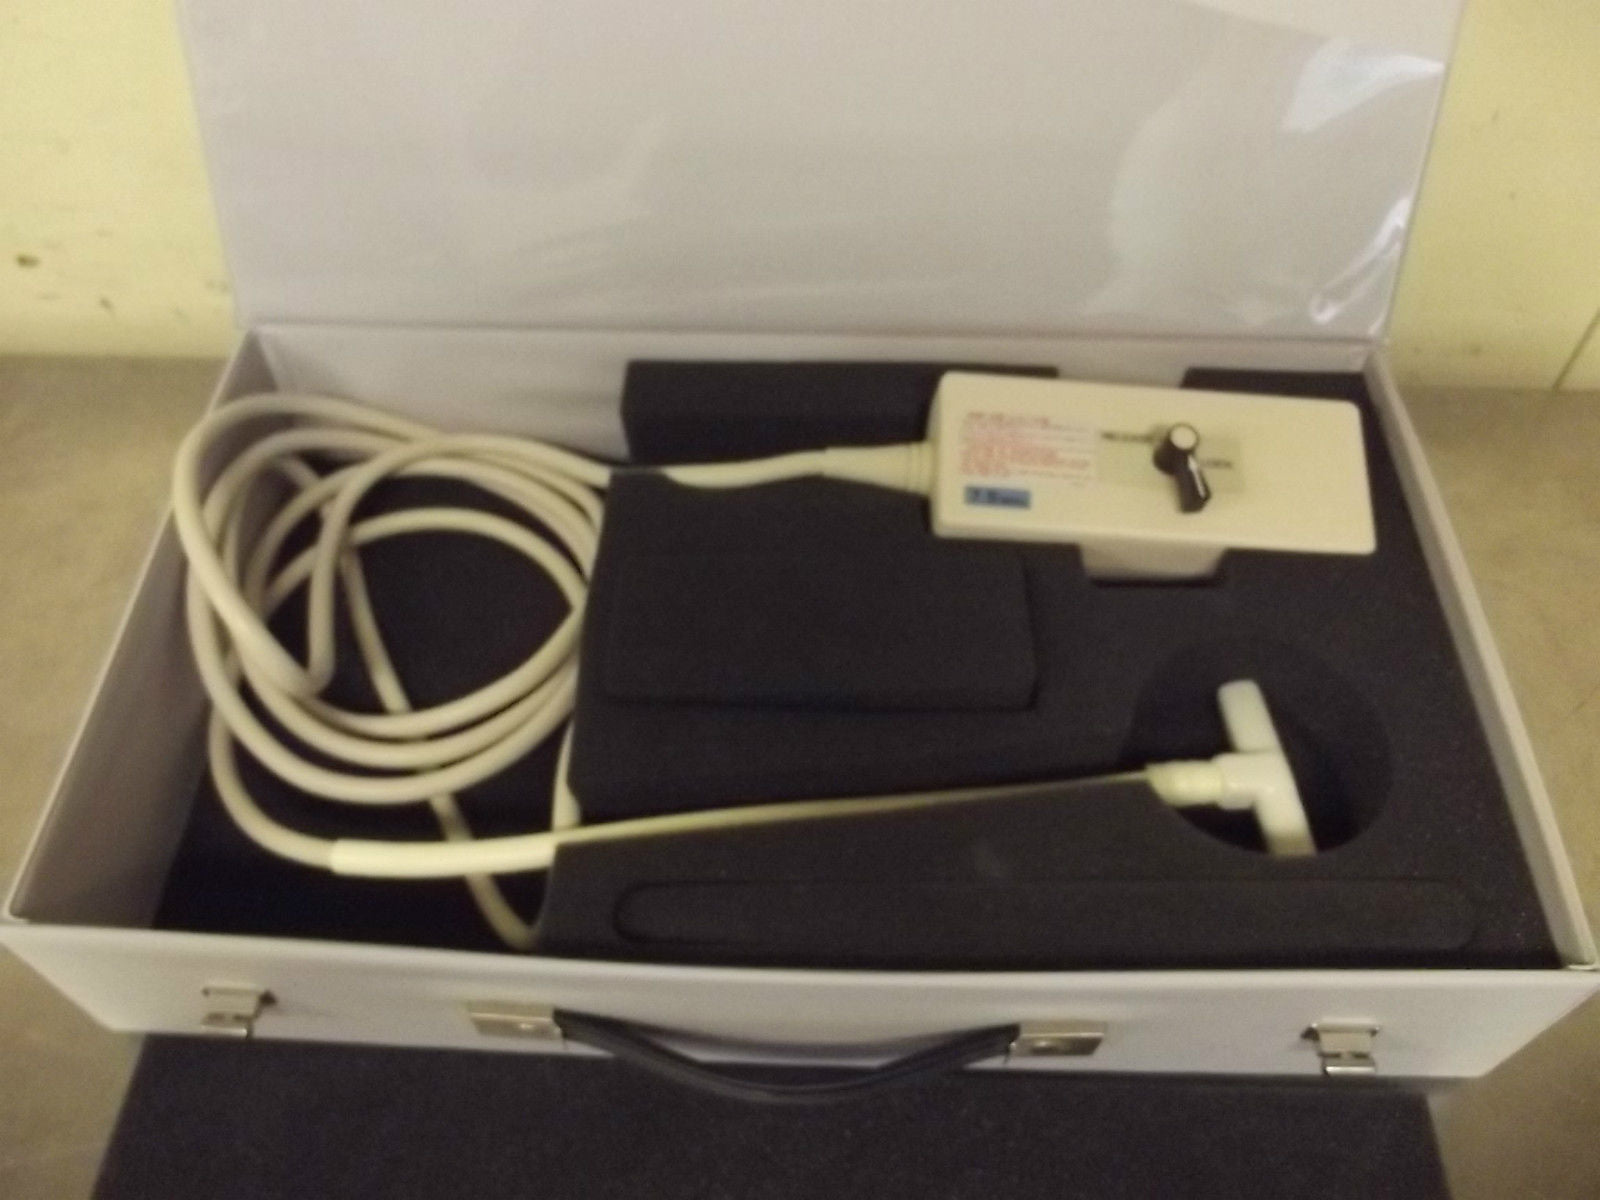

Aloka Ultrasound Probe Model: UST-959-3.5

Aloka Ultrasound Probe Model UST-SSD830P2-5